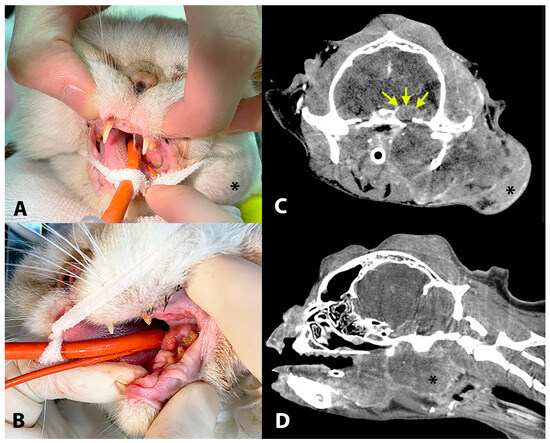

3.1.2. Extracutaneous Lesions

| 10 | ESH | 10 | F | C, M EC, S | Dorsolateral head, Oral cavity, Intracranial | IB | M. canis | ND | ND | ND | ND |